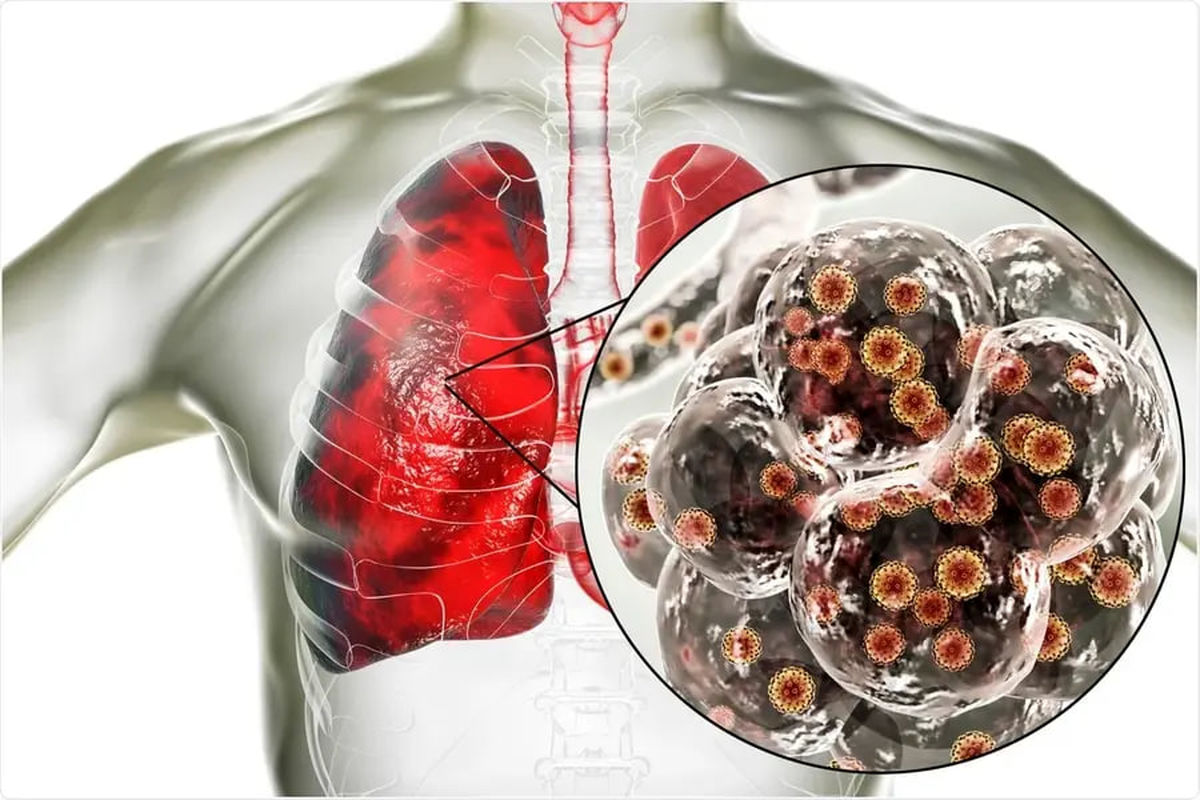

با بازگشت زائران اربعین، افزایش ابتلا به کرونا در برخی استانها مشاهده شده، اما وزارت بهداشت میگوید این تغییر با علائم شدید همراه نبوده و جای نگرانی خاصی وجود ندارد. با این حال، به زائران توصیه شده است در صورت مشاهده علائم، نکات بهداشتی را رعایت کنند.

قباد مرادی، رئیس مرکز مدیریت بیماریهای واگیر وزارت بهداشت، از افزایش نسبت ابتلا به بیماری کرونا در مقایسه با سایر بیماریهای تنفسی خبر داد و گفت: «این افزایش، تغییر قابل توجهی محسوب نمیشود و از آنجا که علائم بالینی غیرمعمول یا شدیدی از بیماران دیده نشده، نگرانی خاصی نیز وجود ندارد.»

رئیس مرکز مدیریت بیماریهای واگیر تصریح کرد: «بر اساس رصدهای انجامشده، تابلوی بالینی متفاوت یا غیرمعمولی از سویه فعلی کرونا که در ایران و جهان بومی شده، مشاهده نشده است. در فصل تابستان به دلیل گرما، فعالیت سایر ویروسها کمتر است و کرونا عامل اصلی عفونتهای تنفسی محسوب میشود.»